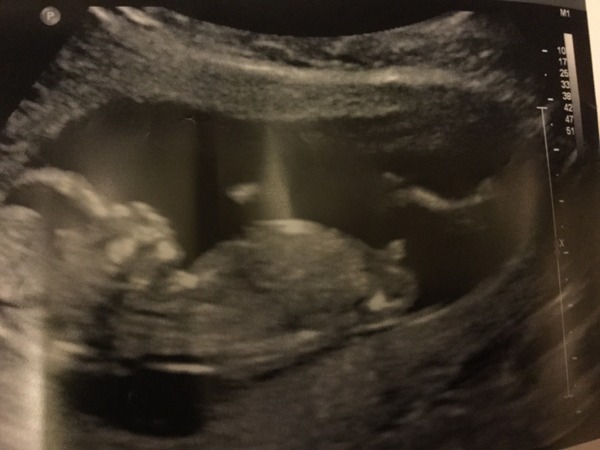

It hasn't properly sunk in for me yet either as my scan was so disappointing. Still don't have a date for my rescan but I'm going to pester the hospital today.